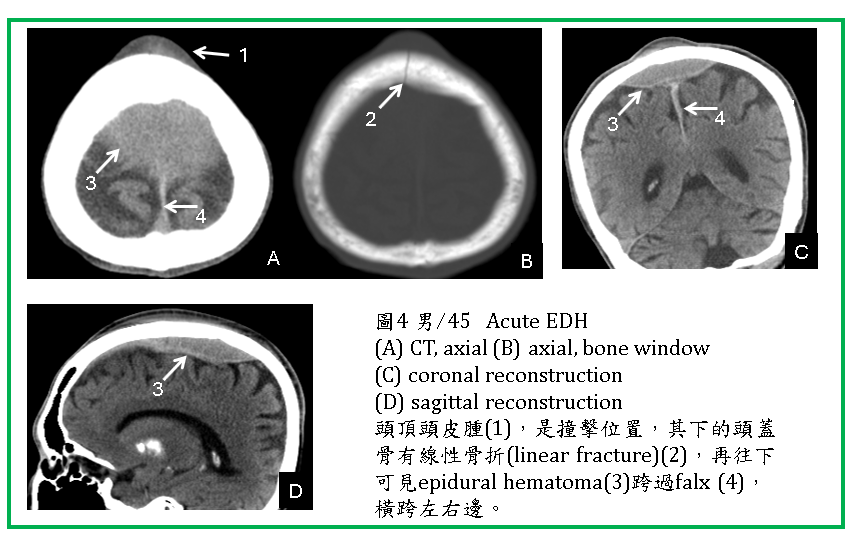

典型的EDH在CT上呈現雙凸形(頭蓋骨與血腫外緣共同構成雙凸形) (圖1-5) ,或稱紡綞形,內為均勻的高濃度血。

EDH通常位於顳、頂葉區,如在額區,可能跨過中線(如falx)到對側(圖4) 。如在後顱窩或枕區,有可能跨過小腦天幕,使小腦天幕上下都有EDH (圖5) 。